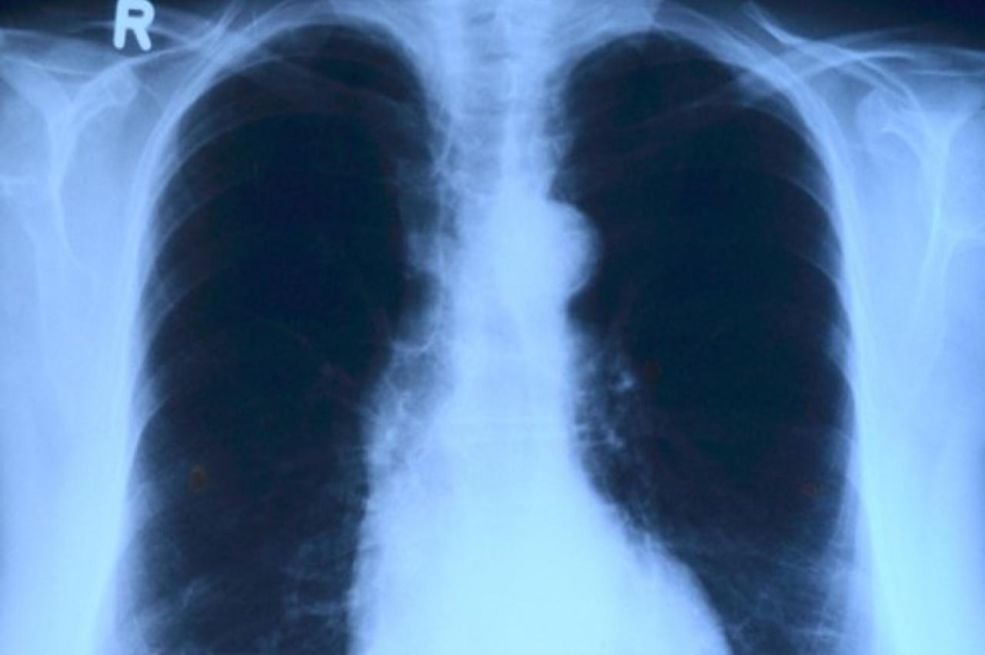

Zdravstvene ustanove ističu da građani ne bi smjeli čekati da simptomi prođu sami od sebe. Pravovremeni odlazak ljekaru jedini je siguran način da se otkrije pravi uzrok problema. Ponekad je potrebno uraditi detaljne analize krvi, dodatne laboratorijske pretrage ili snimanja kako bi se bolest potvrdila ili isključila. Samoliječenje je rizično i može odložiti pravovremeni tretman.